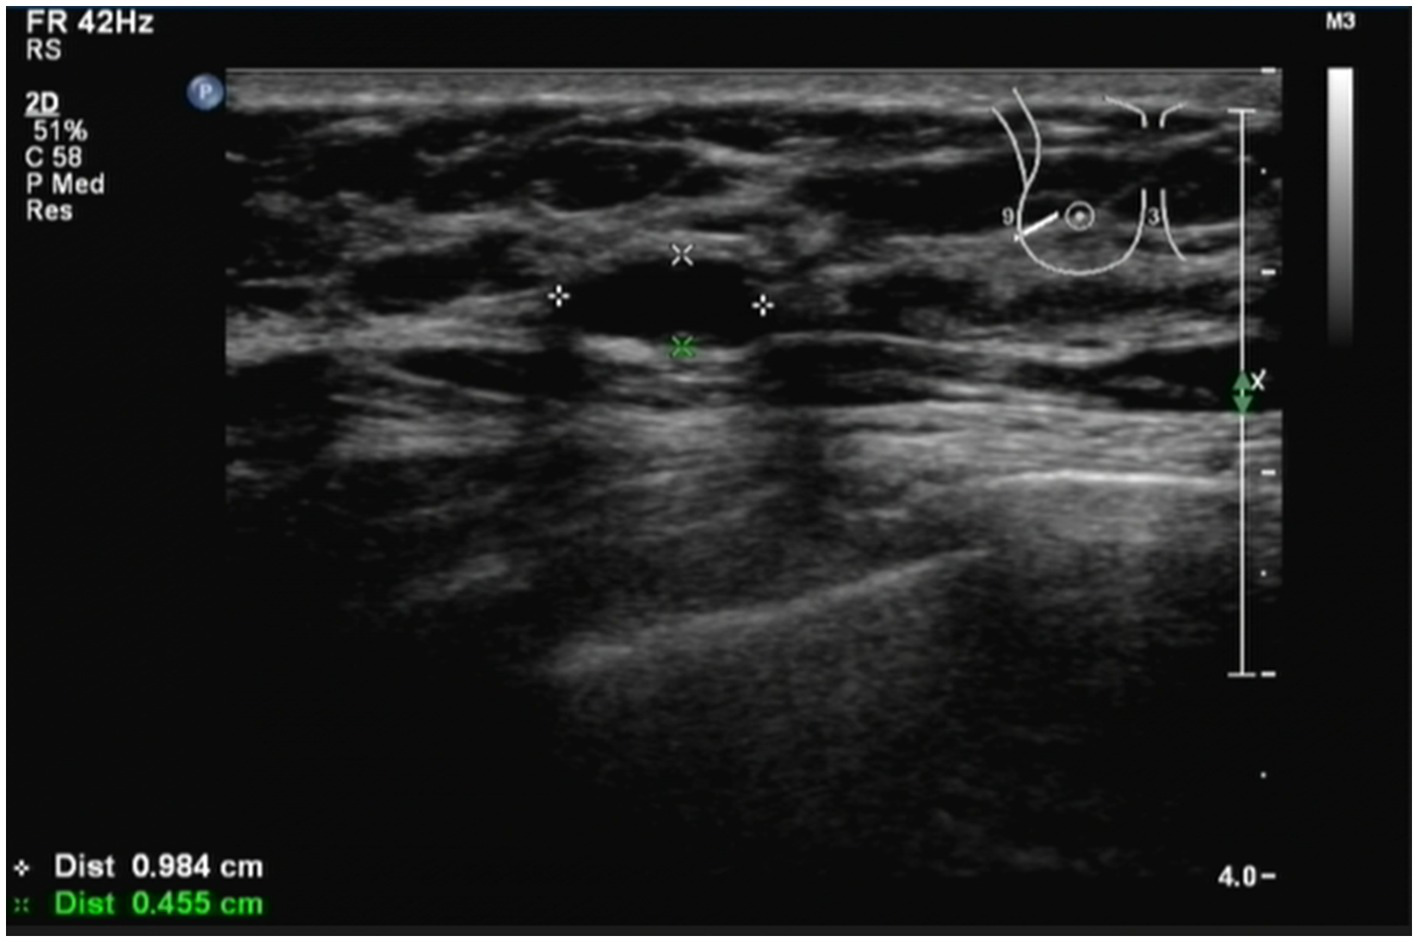

The patient had a history of breast cancer for 2 years. A B-ultrasound examination showed that the tumor in the left breast measured 0.984 cm*0.455 cm (Figure 1) in December 2022. Therefore, the patient was diagnosed with breast cancer at the present hospital. The patient received eight cycles of chemotherapy at another teaching hospital in the province. She underwent left breast lymph node dissection in January 2023, and local radiotherapy was administered 25 times after surgery. Postoperative maintenance therapy included exemestane 25 mg daily and abemaciclib 100 mg two times daily. She had no history of coronary heart disease, blood disease, tuberculosis, hepatitis, kidney disease, mental health disorders, family history of breast/ovarian cancer, or hereditary syndromes. She also denied a history of depression, substance use, or tobacco/alcohol consumption. The patient had a 10-year history of type 2 diabetes mellitus, managed with acarbose 100 mg orally three times daily (TID). She self-reported good glycemic control, though no recent HbA1c data were available. In addition, she had a 10-year history of hypertension, treated with losartan potassium 50 mg orally once daily (QD), and reported stable blood pressure without documented hypotensive episodes. No diabetic complications (e.g., retinopathy and neuropathy) or end-organ damage related to hypertension (e.g., renal impairment) were noted in her medical records. She did not experience nausea, headache, chest distress, diarrhea, or any other symptoms.

Figure 1

Patient was diagnosed with breast cancer by B-ultrasound. B-ultrasound examination showed that the size of the tumor in the left breast was 0.984 cm*0.455 cm. The patient had a history of breast cancer for 2 years.